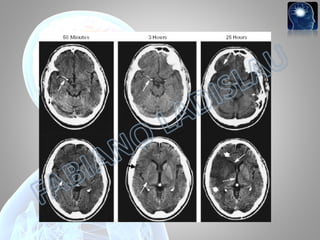

• AVC isquêmico; •Detectado três horas após o evento, quando a TC nada mostrava.